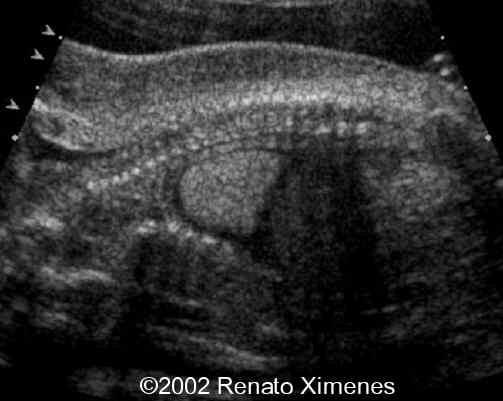

The cystic hygroma extends down the back of the fetus and pleural effusions are visible:

case0072-3

case0072-4

case0072-5

The critical image is the soft-tissue webbing of the rhizo-mesomelic joints. This is more than the simple contractures seen in many of the arthrogryposis.

case0072-7

case0072-8